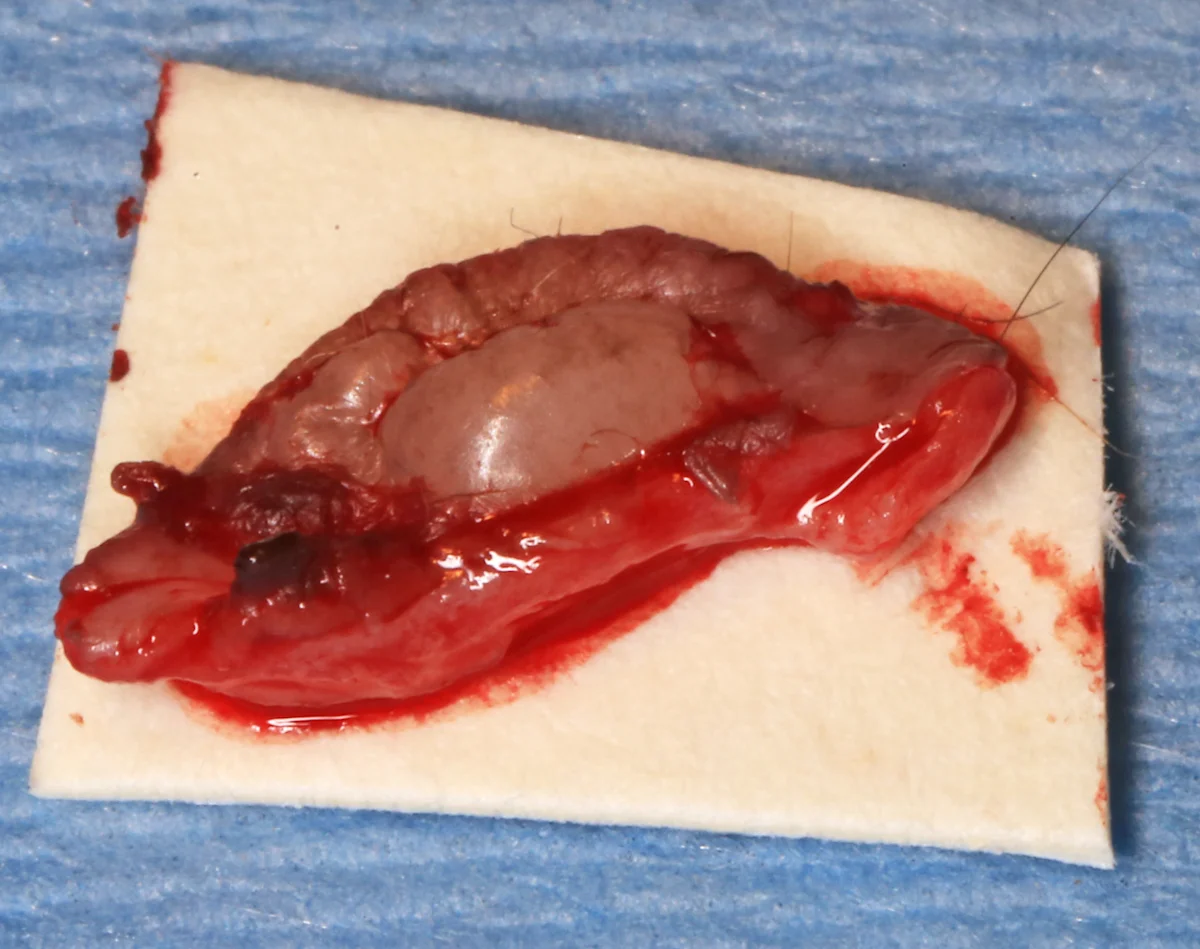

Due to COVID-19 pandemic lockdown restrictions, there was a 2-day delay before multiple elliptical and 6- to 8-mm punch skin biopsies were collected with the patient under general anesthesia (Figure 7). The skin biopsy samples were submitted with urgent request to a dedicated dermatohistopathology team. Results showed blister formation at the dermoepidermal junction where the epidermis had separated from the underlying dermal stroma, likely through the basement membrane zone (Figure 8). Neutrophils were the predominant cell type, with no evidence of acantholytic keratinocytes, epidermal necrosis, or apoptosis.

FIGURE 7 Excised coalescing vesicles from the right pinnal margin on biopsy